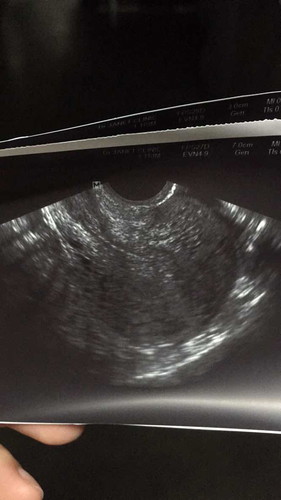

ตั้งครรภ์ 5w แต่ซาวน์ไม่เจอถุงครรภ์

จากประจำเดือน นับได้ 5w ค่ะ แต่เมื่อวานซาวน์ช่องคลอดไม่เจออะไรเลยค่ะ เป็นไปได้ไหมคะ ว่าครรภ์ยังอ่อนมาก เมื่อเช้าตรวจยังขึ้น 2 ขีดอยู่เลยค่ะ แม่ๆคนไหน เป็นแบบนี้ไหมคะ ช่วงท้องอ่อนๆ กังวลมาก เพราะเคยท้องลมปีที่แล้วค่ะ ขอบคุณมากค่ะ